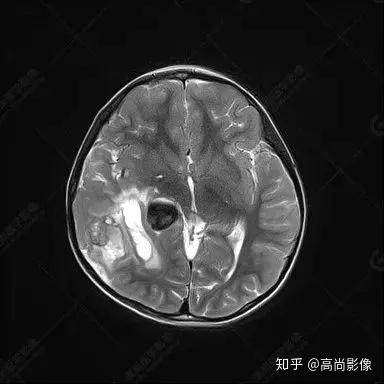

右側(cè)顳葉腫瘤切除術(shù)后(具體不詳):右側(cè)顳部骨質(zhì)不連續(xù)呈術(shù)后改變,右側(cè)顳葉術(shù)區(qū)見片狀長T1長T2信號影,F(xiàn)LAIR呈低信號;術(shù)區(qū)后方右側(cè)顳枕葉見一巨大占位性病變影,邊界欠清,大小約6.2×5.8×4.3cm(前后×左右×上下),信號不均勻,T1WI呈等稍低信號間雜少許高信號,T2WI呈高稍低混雜信號,DWI示部分病灶彌散受限,相應(yīng)ADC圖減低,磁敏感序列見部分呈極低信號,增強(qiáng)掃描可見明顯不均勻強(qiáng)化,鄰近硬腦膜及小腦幕增厚并明顯強(qiáng)化;另延髓右前方及右側(cè)橋小腦角區(qū)見一不規(guī)則形異常信號影,大小約3.2×1.3×3.7cm(左右×前后×上下),呈長T1稍長T2信號,F(xiàn)LAIR呈等信號,DWI未見受限,增強(qiáng)后明顯均勻強(qiáng)化,鄰近腦膜明顯強(qiáng)化。鄰近腦實質(zhì)及右側(cè)顳角明顯受壓;左側(cè)大腦半球未見局灶性信號異常,中線結(jié)構(gòu)稍左移。

右側(cè)顳葉腫瘤切除術(shù)后:現(xiàn)術(shù)區(qū)后方右側(cè)顳枕葉及延髓右前方占位,右側(cè)顳枕部硬腦膜及小腦幕明顯強(qiáng)化,結(jié)合既往影像資料,考慮為胚胎源性惡性腫瘤,如非典型畸胎樣/橫紋肌樣瘤(AT/RT)或原始神經(jīng)外胚層腫瘤(PNET)。

術(shù)后隨訪病理結(jié)果:非典型畸胎樣/橫紋肌樣瘤。

非典型畸胎樣/橫紋肌樣瘤(AT/RT) 是一種高度惡性中樞神經(jīng)系統(tǒng)腫瘤,臨床罕見,臨床表現(xiàn)無特異性,好發(fā)于 5 歲以下兒童,尤以 3 歲以下多見,在兒童原發(fā)性中樞神經(jīng)系統(tǒng)(CNS)腫瘤中占 1%~3%。該腫瘤體積一般較大,幕上大于幕下,有明顯的占位效應(yīng)。該腫瘤成分復(fù)雜,囊變、出血、壞死常見。因此 AT/RT信號混雜,囊性部分呈 T1WI低、T2WI高信號,增強(qiáng)后不強(qiáng)化;若瘤體出血,囊內(nèi)可見T1WI稍高信號、T2WI低信號,實性部分在 T1WI上呈混雜等、低信號,在T2WI 及 T2-FLAIR上呈混雜等高信號,增強(qiáng)掃描后大部分呈環(huán)形條帶樣明顯強(qiáng)化,中心壞死區(qū)不強(qiáng)化。另外,該腫瘤實性成分在DWI上呈高信號,說明腫瘤細(xì)胞核密集,水分子擴(kuò)散明顯受限,提示該腫瘤惡性程度高,容易復(fù)發(fā)及轉(zhuǎn)移。